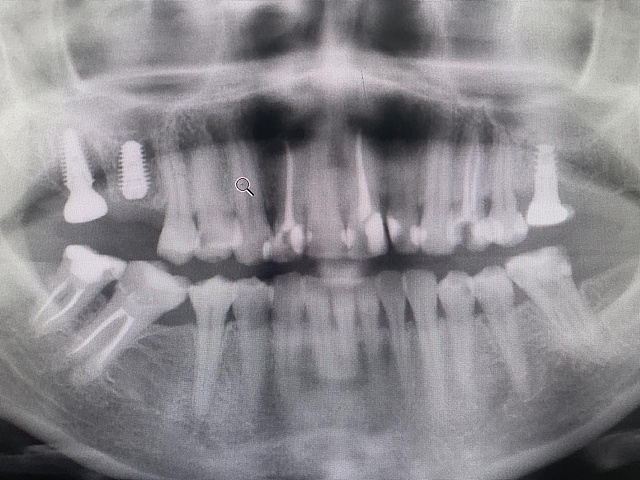

Пациент: С., женщина, 40 лет

Обратилась с жалобами на отсутствующий 16 зуб и разрушенный 17 зуб.После осмотра и чтения КЛКТ снимка принято решение о классической имплантации в области 16, и одномоментной в области 17.

Так как костное предложение было богатое, имплантаты выбраны 16 зуб — 5,5х9,5 и 17 — 5,5х11.

Для одномоментной имплантации в области 17 зуба размер подходил идеально, поэтому его установка заняла: 1 раз сверка размер финальной фрезы под размер имплантата, а затем его установка. Торк 16 зуба 40 Нм, торк 17 зуба, 40 Нм.

Прогноз благоприятный.

Снимок 2018 года.